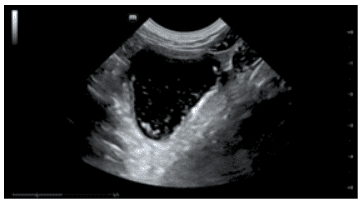

A. In short, yes! Incredibly so, in fact. It is important to note that they have been designed with a specific purpose in mind. Namely, point-of-care ultrasound (POCUS), and the flexibility they offer is, frankly, stunning. Typically, they offer two or more transducer options. Either by virtue of interchangeable ‘heads’, or being ‘double-ended’, with different transducer types on each end. Wireless transmission of image data to a smart device (phone, tablet, etc.) enables viewing anywhere, and image quality is surprisingly good. They wouldn’t replace a traditional high-end system, certainly, but in the context of the relatively recent rise in popularity of POCUS, they are something of a game-changer. Light, portable, robust, low-cost, and high-quality, I suspect it won’t be long before they’re as ubiquitous and indispensable as a stethoscope.

Canine spleen and pancreas, GE VScan Air Canine intussusception, GE VScan Air